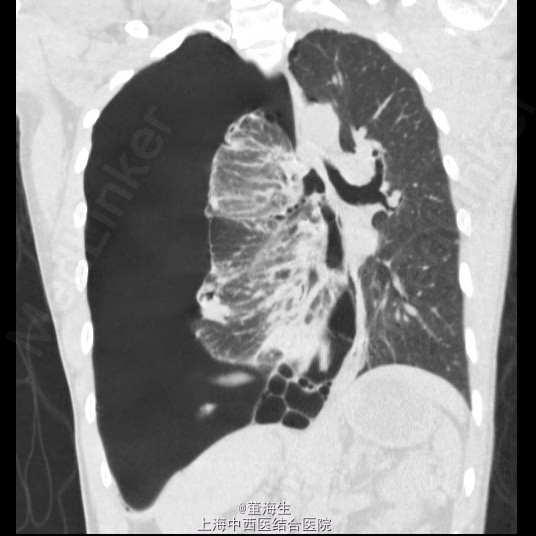

患者,男,39岁。 1.主诉、现病史:患者因为“突发胸闷1日”入院。患者入院当日1:00突觉胸闷,至约16:00来院就诊,辅查胸部CT后如附图1,附图2。既往无类似发作史。 2.查体:患者神清,精神状态良好,生命体征平稳,无气促。右肺听诊呼吸音消失,左侧正常。 3.辅助检查:胸部CT表现如附图1,附图2,血常规提示120g/L,血红蛋白压积正常。 4.诊断:右侧自发性血气胸。 5.处理方案: ①入院后明确诊断,即刻取右侧锁中线第2肋间行胸腔闭式引流。置入8F一次性引流导管一根(该导管头端卷曲,有多个侧孔),导管接水封瓶。静脉给予抗生素及凝血酶,床边心电监护。 ②闭式引流后3小时内引流大量气泡并引流血性液1100ml,即刻复查血常规提示Hgb102g/L。 ③引流3小时后观察引流液不再明显增加,至第二日晨共1400ml血性液,复查血常规仍为102g/L。 ④引流第二日起引流液色逐渐转至浆液性,至入院第6日共引出液体2100ml,负压波动消失,每日引流量少于100ml。予夹闭引流管。 ⑤夹管24小时后复查胸部CT,结果见附图3,附图4。当日予拨除胸腔闭式引流。 6.随访复查:出院后1周,门诊复查胸片及胸水B超,提示无气胸及液胸。 7.分享病例的体会: 实习时老师教导,每小时胸引>200ml血性液,应急诊行剖胸探查。该病例实际治疗时因读片提示胸腔大量积液,保守估计该有1500ml左右,且发病至入院已约15小时,且患者生命体征平稳。故治疗时采取的思路为先放尽积液再计算单位时间内引流量,同时密切观查患者生命体征变化。 此病例没有盲从缺少先决条件的临床条例,免除了患者的手术痛苦。 是否得当请广大同行指正!